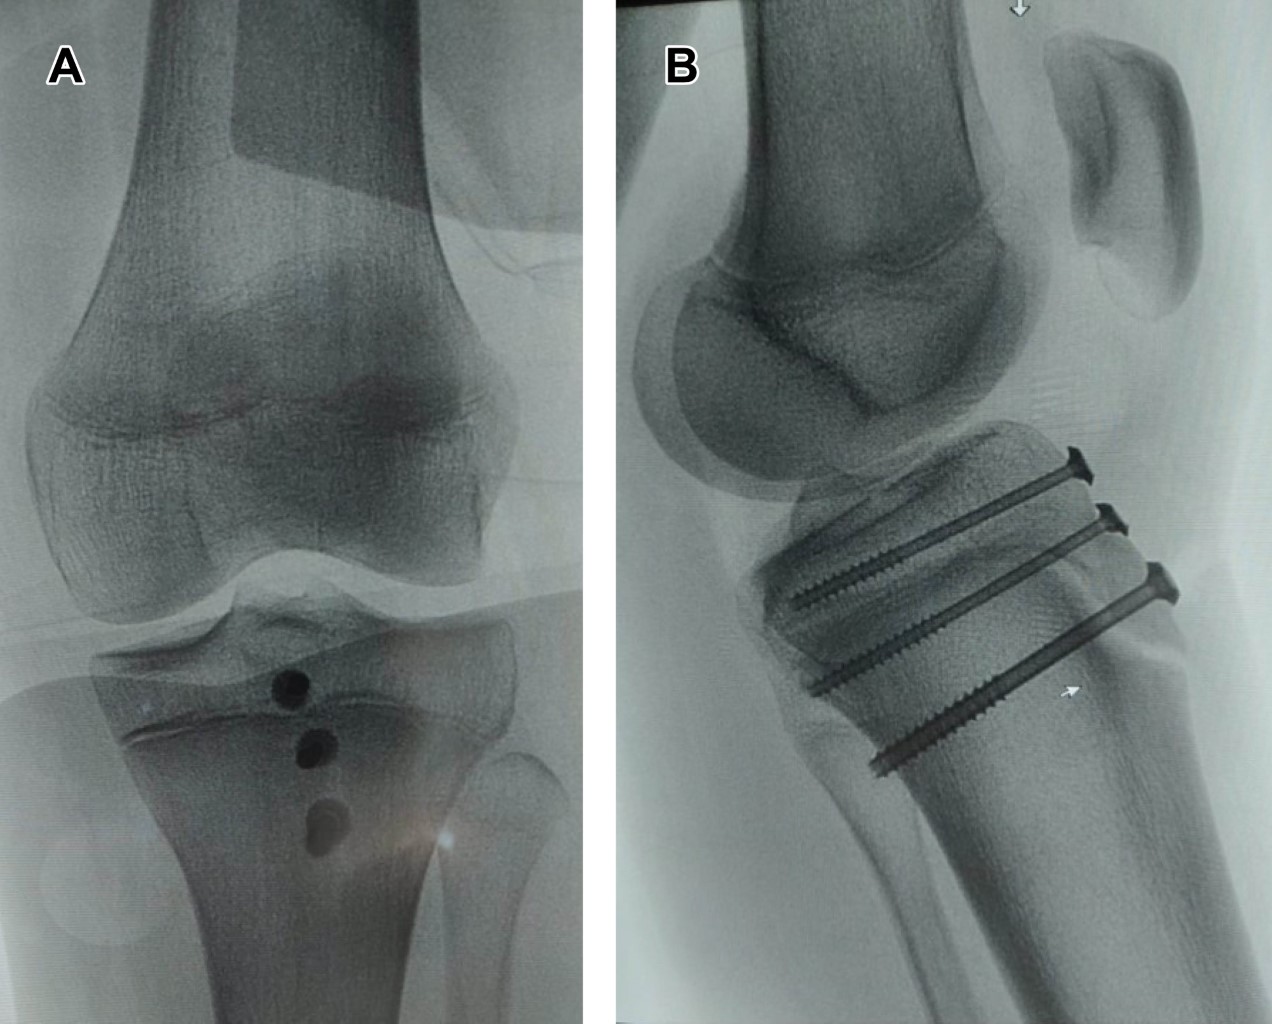

Masculino de 12 años, con estatura de 178 cm, jugador de baloncesto desde los ocho años; quien, realizando ejercicios de marcha en cuclillas, en el momento de cambiar a posición de pie, refiere dolor intenso en rodilla izquierda, acompañado de chasquido, deformidad, e imposibilidad para la función. Es trasladado a urgencias, efectuando diagnóstico de fractura avulsión de tuberosidad anterior de la tibia, corroborando ATT tipo III de Watson y Jones (Figuras 1 y 2), se realizó reducción y osteosíntesis (Figura 3).

Figura 1